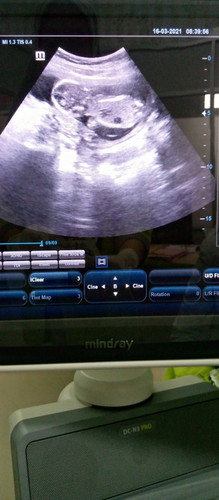

Ini aku baru USG anak pertama aku masuk kehamilan 15 Minggu bun. Tapi perut masih kecil belum buncit

janinnya juga baru segede apa bun.... asalkan sehat anaknya, aman..